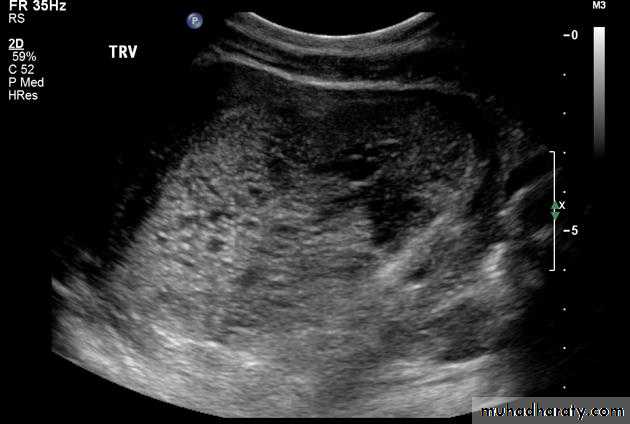

US of partial H.mole

This slide show patial H.mole + vesicles + fetal tissue